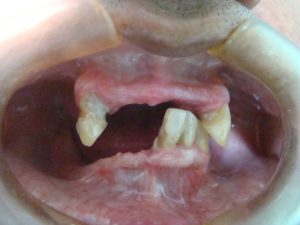

Veja os resultados de nossos pacientes

Implantes dentários são suportes ou estruturas de metal (normalmente de titânio) posicionadas cirurgicamente no osso maxilar abaixo da gengiva para substituir as raízes dentárias. Uma vez colocados, permitem ao dentista montar dentes substitutos sobre eles.